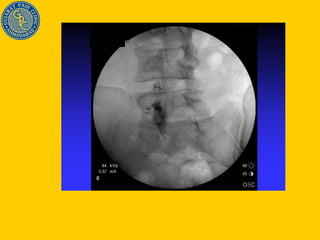

Injection Technique done with C-arm fluoroscopic device Steroid Reverses effect of inflammatory mediators Stops inflammation cascade Helps in healing annular tear Stabilizes cell membrane Delays pain impulse conduction Gives pan/ inflammation free time for disc herniation to settle down by natural process (Natural history of disc disease)

Injection Technique